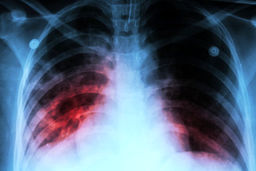

خبرمهم: پزشک معالج علی انصاریان ضمن تشریح وضعیت بیماری او، گفت: متاسفانه بیش از ۸۰ درصد ریه ایشان درگیر بیماری شده است…

عامل آسیب ریه در اثر ابتلا به کووید ۱۹ شناسایی شد

خبرمهم: محققان دریافتند بقای سلولهای غیرطبیعی حاصل از ابتلا به کووید ۱۹ در ریه، مهمترین عامل بروز آسیبهای ریوی محسوب …